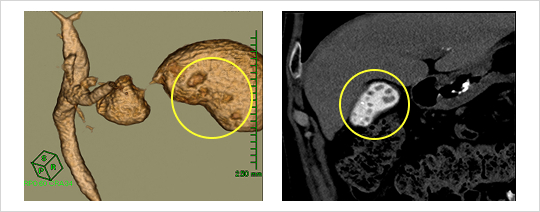

CT(X線断層撮影)

お腹の輪切りの写真で、お腹の中の臓器の関係がよく分かります。ただし写らない石もあります。